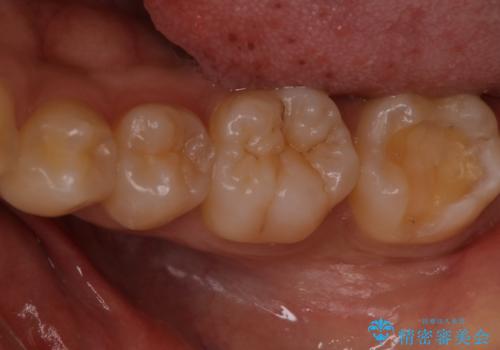

- 検査の結果、虫歯が見つかった患者様です。

白く目立たないものでの治療をご希望されたため、セラミックインレーでの治療となりました。

適合の良いセラミックインレーで修復することで見た目の綺麗さを保ったまま治療することができます。